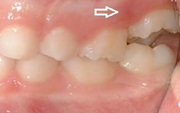

Koonilise kujuga lisahammas ülemiste tsentraalsete lõikehammaste vahel.

Suulaepoolt lõikunud koonilise kujuga lisahammas